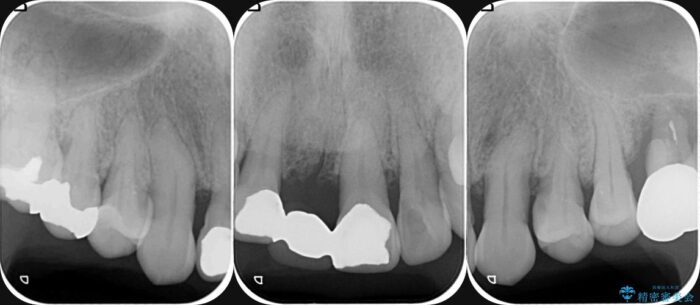

検査の結果、歯周ポケットの測定値は4-6mm程度の値が全顎にわたって認められ、中等度歯周病の状態です。

歯を今後残し、歯周病の状態を改善するため、歯槽骨の再生治療をおこなったのち、歯周ポケットの除去、セラミックブリッジの製作を行う治療計画を実行していきます。